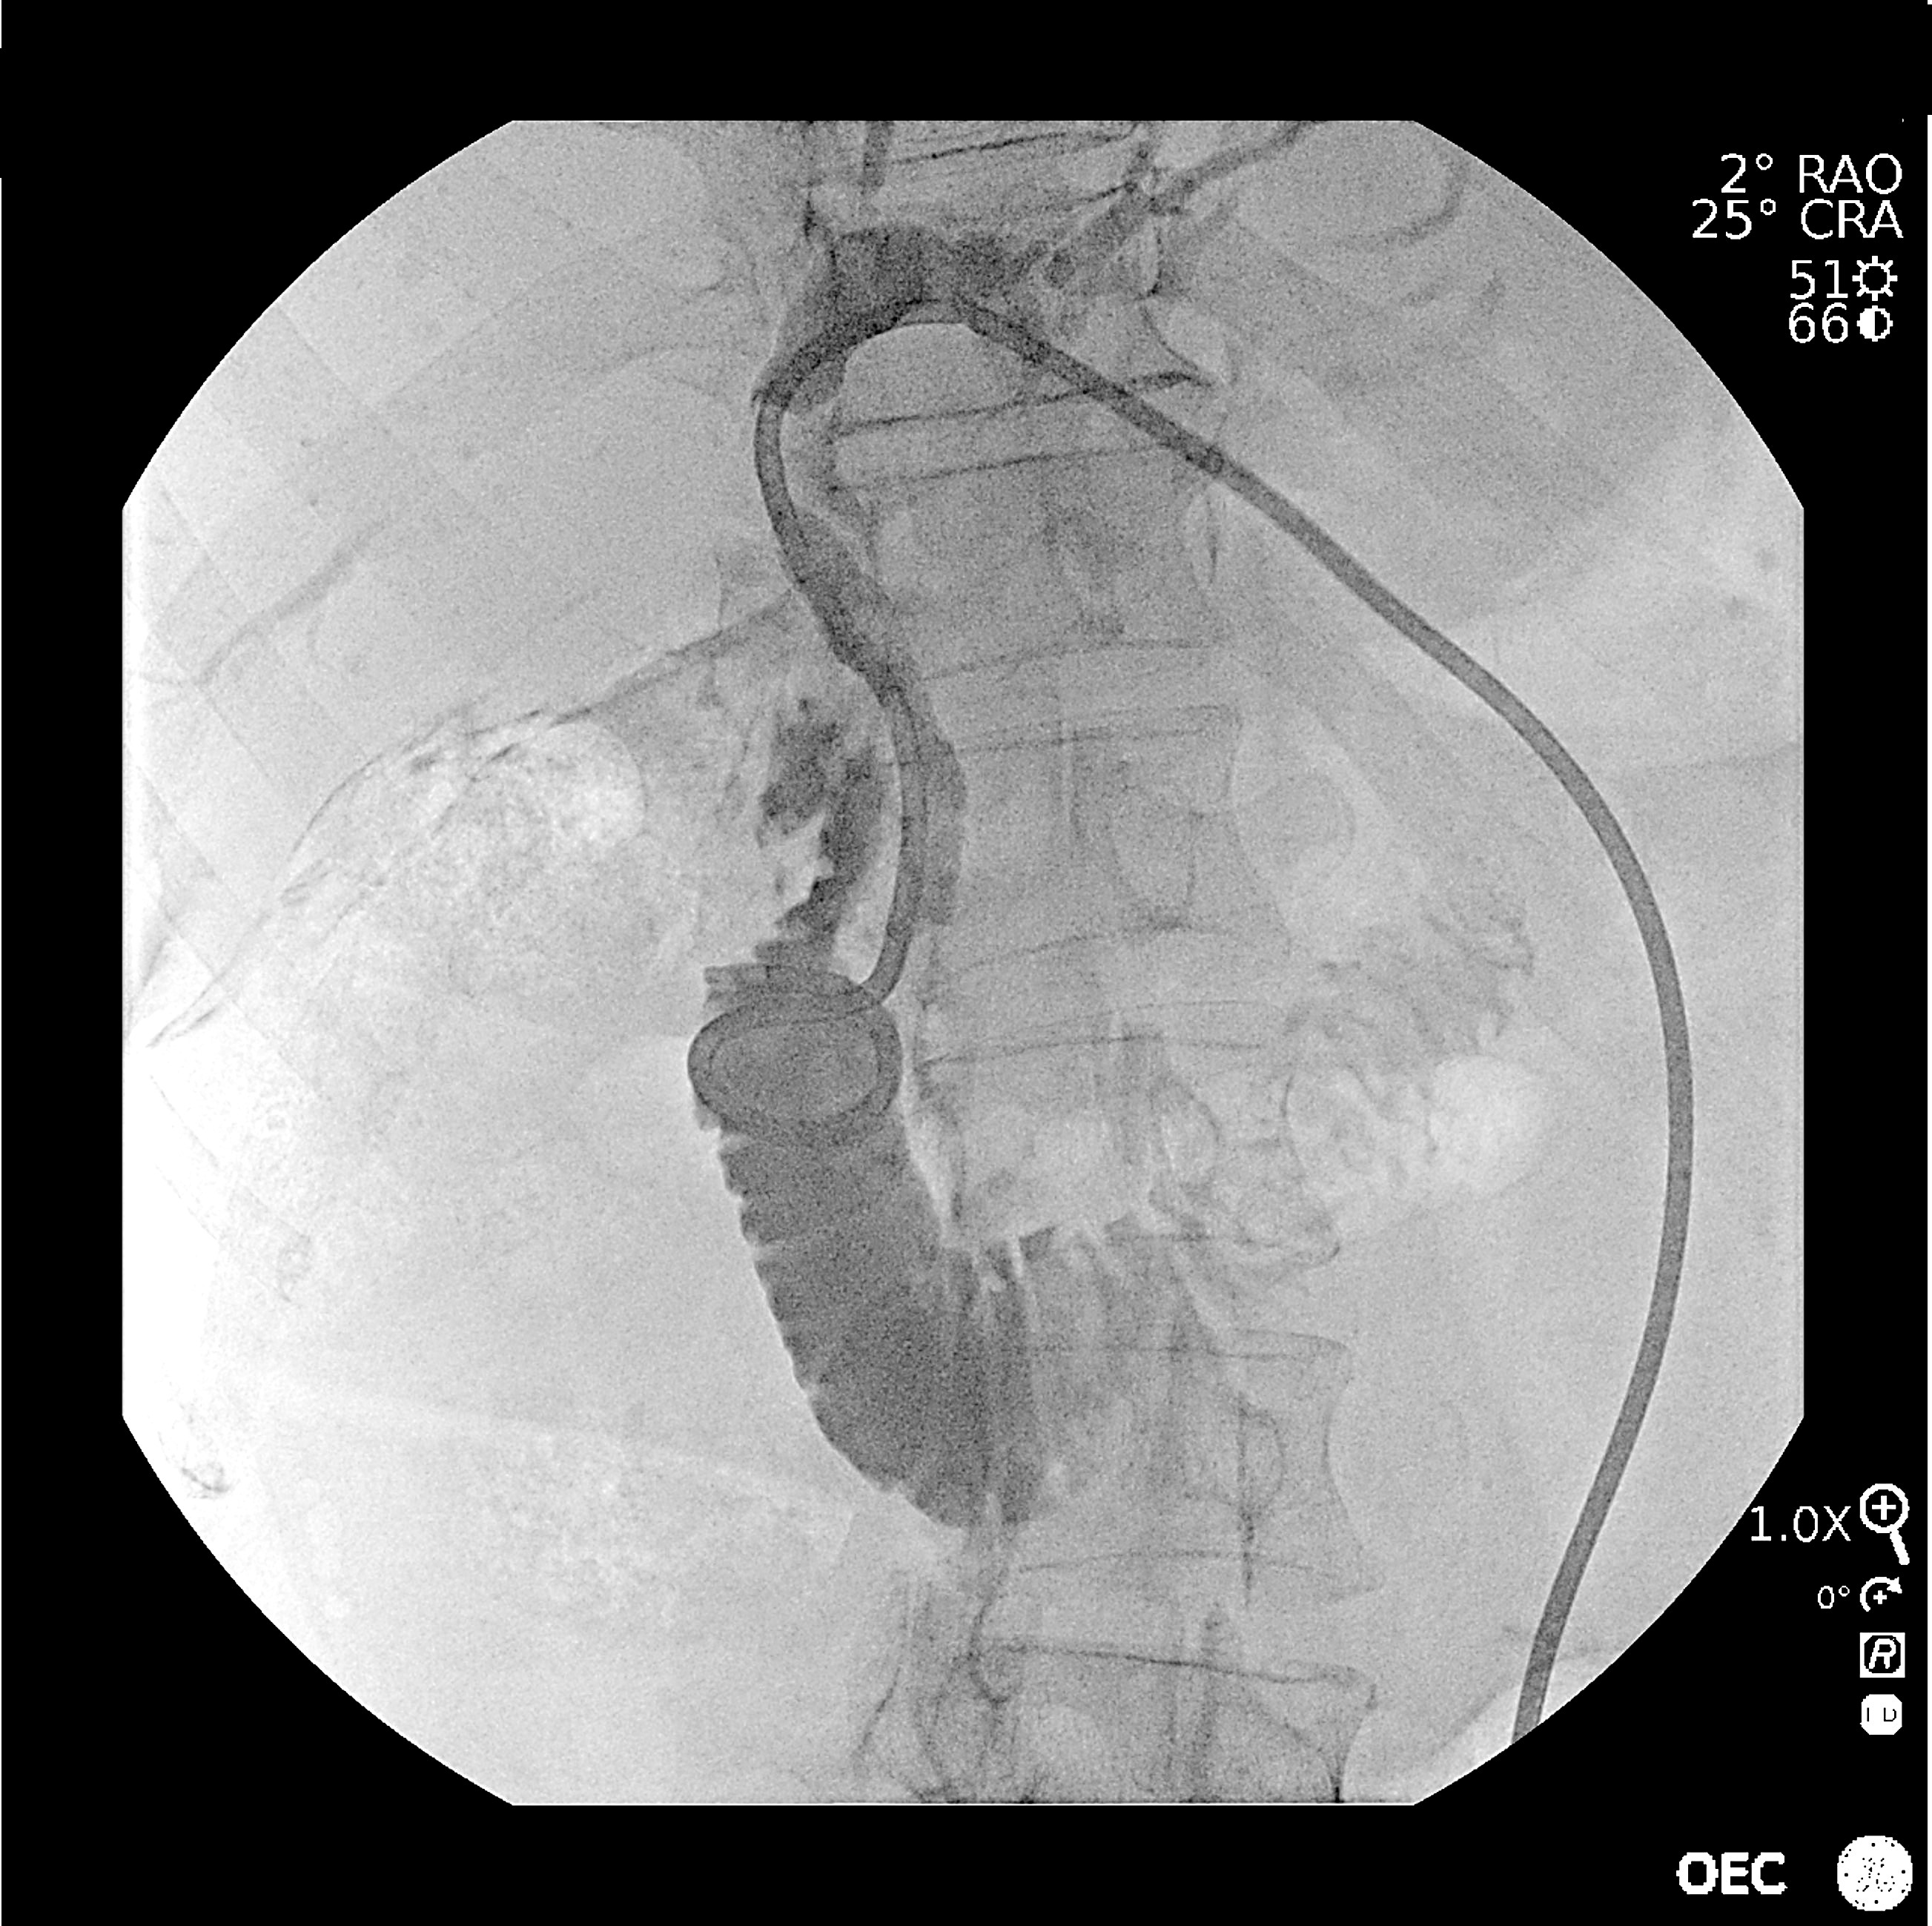

Complete portal embolization before right hepatectomy

Portal embolization is an interventional radiology procedure performed under general anesthesia. It is a specific embolization of the smallest capillaries of the portal system. It aims to deprive segments of the liver from their blood supply. This procedure is performed before hepatectomy, surgical resection of the liver’s segments. The selective embolization procedure preserves the segments of the liver to remain and promote its compensatory hypertrophy. In the present case, the procedure consist of embolizing the right segments of the liver.

The procedure includes two main steps: a biliary drainage to prepare the patient for surgery and the embolization itself. Access to the portal vein is performed through a lateral percutaneous puncture under ultrasound guidance.

A portography, or image of the injection of contrast agent into the portal circulatory system, is performed. This injected fluoroscopic image allows for mapping the liver and identifying the vessels in the anatomical region of interest. It enables ultra-selective micro-catheterization of the liver vessels. The navigation of the endovascular tools in the liver is done in roadmap mode based on the previously performed angiography. This method allows selective and specific access to the different small branches of the portal system. An ultra-specific embolization of all the vessels and micro-vessels in the right part of the liver is then performed using biological glue. This glue helps to obstruct particularly fine vessels. Once all the vessels are obstructed, a final angiographic control is performed to ensure that the vessels are properly obturated and that blood flow no longer irrigates the part of the liver that will be removed.

Step 2: Embolization of the portal system

5. Fluoroscopy during portal system puncture.

6. Angiography confirming the position of the catheter in liver.

7. Digital Subtracted Angiography of the portal system.

8. Angiography at the beginning of the ultra-selective embolization of the portal system.

9. Portography of final control showing obstruction of the portal system of the right part of the liver to be resected.